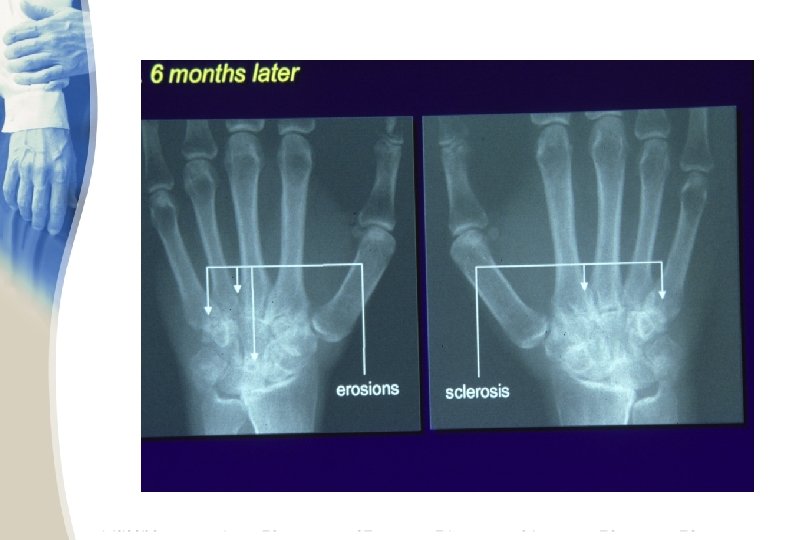

RHEUMATOID ARTHRITIS • Labs – joint fluid examination is valuable. The fluid is translucent to opaque and has between 3000 and 50, 000 WBCs /micro. L. There are 50% or more polymorphonuclear leukocytes. The culture is negative. • X-ray – of all the laboratory tests, x-ray changes are most specific for rheumatoid arthritis. However, they are not sensitive and usually are negative during the first 6 months of the disease

RHEUMATOID ARTHRITIS • X-rays – The earliest changes occur in the wrist or feet and consist of soft tissue swelling and juxta-articular demineralization. – Later, diagnostic changes consisting of joint space narrowing and erosions develop. The erosions are first seen at the ulnar styloid and at the juxtaarticular margin, where the bony surface is not protected by cartilage. – Diagnostic changes also occur in the cervical spine with C 1 -2 subluxation, but this can take several years to develop.

Bony erosions

juxta-articular osteoporosis marginal erosions narrow joint space